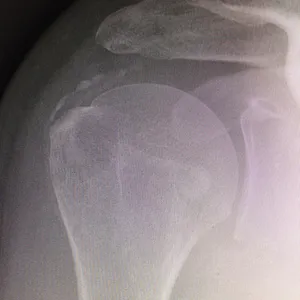

Pour des raisons mal connues (a priori indépendantes du type d’alimentation), des dépôts semblables à de la craie peuvent apparaître au sein des tendons de la coiffe des rotateurs.

- Elles sont responsables d’un conflit sous-acromial : lors de l’élévation du bras, les tendons calcifiés « accrochent » l’arche osseuse de l’acromion, entraînant une douleur aiguë.

- Elles augmentent le risque de rupture tendineuse : proportionnellement à leur taille, elles fragilisent les fibres du tendon.

Ces calcifications sont trop souvent banalisées car elles sont souvent indolores. Malheureusement ces calcifications désorganisent et détruisent à bas bruit les fibres des tendons au sein desquels elles se développent. Laisser grossir ces calcifications augmente le risque de rupture tendineuse lors d’un traumatisme ou d’un effort. Le traitement médical a l’inconvénient de calmer la douleur mais de laisser la calcification grossir à bas bruit. Dès que la taille de la calcification devient conséquente par rapport au tendon, la ponction lavage doit être proposée pour stopper son évolution.

Suivi radiographique